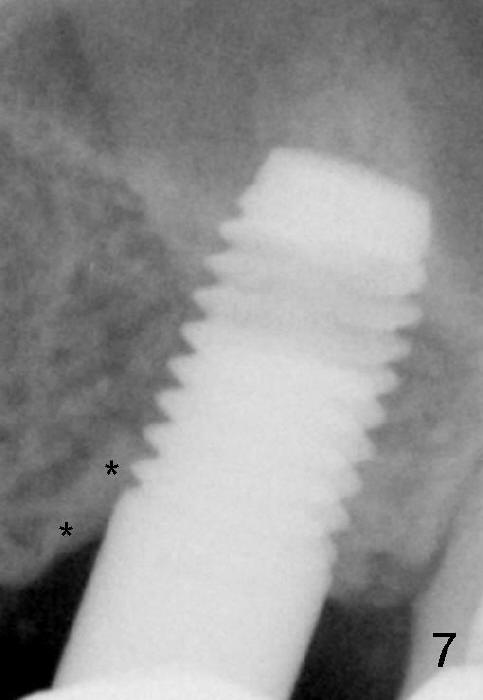

A 5x14 mm cylindrical implant (Fig.3 I) was inserted with elevation of the apparent sinus floor (>, no allograft used in case of sinus infection). Seven months postop, the density of sinus floor increases (Fig.4 <). The implant is stable and processed for crown (Fig.5 C, different view of the lifted sinus floor (<)). While sinus floor density is decreasing, the mesial and distal bone density is increasing 6 months (Fig.6), 1 year 6 months (Fig.7) and 3 year 6 months (Fig.8) post cementa-tion.